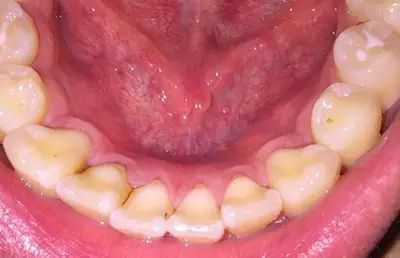

由于长期口腔卫生条件不佳,大量细菌、色素沉积在牙齿上,尤其是根部,形成牙结石刺激牙龈,这种牙结石呈黄色或者黑色,刷牙很难刷掉,可通过洗牙去除。

当龋齿已经是深龋或者是中龋的时候,蛀洞相对比较深,非常容易进行分辨。牙体的组织受到细菌侵蚀之后形成一定的龋洞,而由于洞内的大量黑褐色腐质的存在,龋洞的周围受到感染的牙体组织也显现黑褐色。

长期抽烟、喝咖啡喝茶等都可能产生色素沉积在牙齿上,造成牙齿发黄、发黑。牙齿是非常容易长烟斑的,因为烟里面含有“咖啡碱”,在酸性口腔之中反应非常容易形成烟斑,长年累月下去,牙齿上面的烟斑就非常多了。

而茶渍的形成则是与烟斑相类似。由于茶叶里面含有“生物碱”,在酸性的口腔之中反应或许就会形成茶渍。